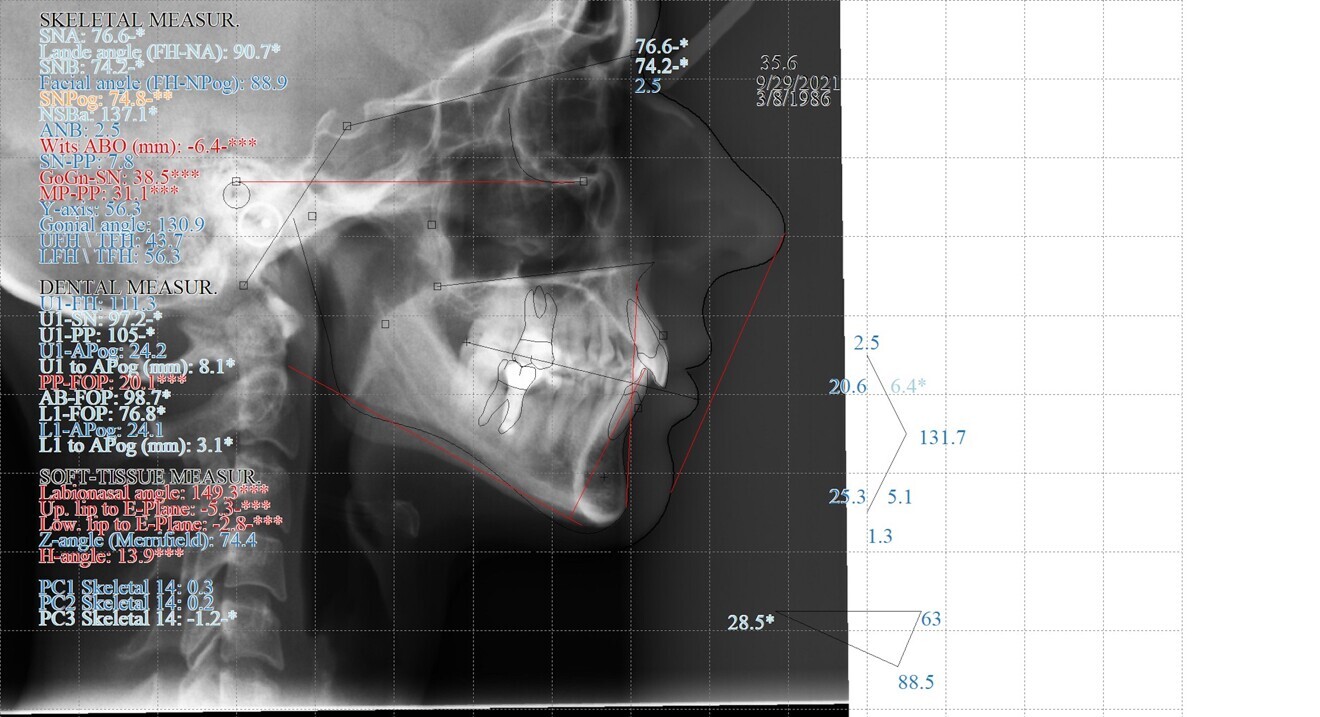

Fig. 4: Pretreatment cephalometric radiograph and analysis.

The third molars were not present. The evaluation of the cephalometric radiograph (Fig. 4) showed a retrognathic mandible (SNB: 74.2°) and normal inclination of the incisors, both maxillary (Ui–FH: 111.3°) and mandibular (Li–APog: 24.2°).

Regarding the final cephalometric analysis, the facial height (LFH: 56.5 mm) and measurements of soft tissue remained the same. The inclination of the maxillary incisors was well preserved (Ui–FH: 115.8°), and the mandibular incisors were slightly proclined (Li–APog: 30°; Fig. 16).